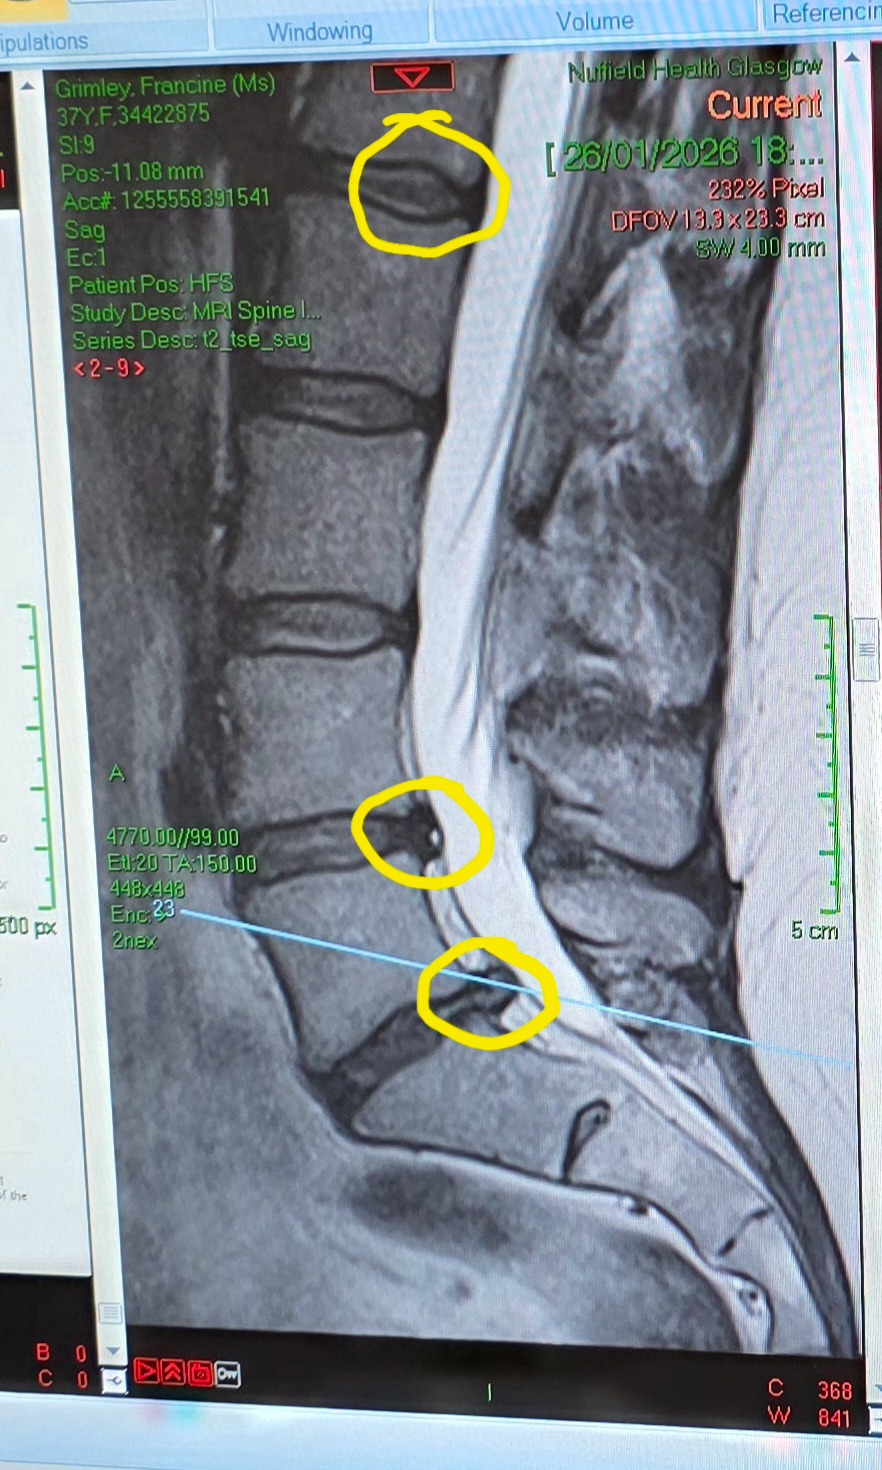

Then there’s my spine...

I have degenerative disc disease, with two ruptured discs in my lower back that are starting to compress my spinal cord and nerve. Sometimes my left leg just gives way. The pain is the worst I’ve ever experienced. Right now, I’m in a stage of pain management - this isn’t something that gets better. It’s something I have to manage… until the likely reality of major spinal surgery, replacing multiple discs. If things progress, I could lose the ability to walk, and even control basic functions like my bladder and bowels.